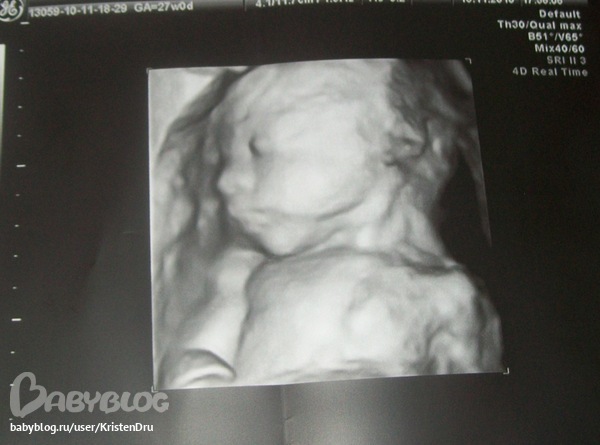

ну она наверное у меня мин 10 пыталась нормальный ракурс выбрать)))Ну , а само узи в 4d наверное интересно. ведь там все движения малыша записывают на диск и все там четко видно... это фото я на 24 неделе беременности делала